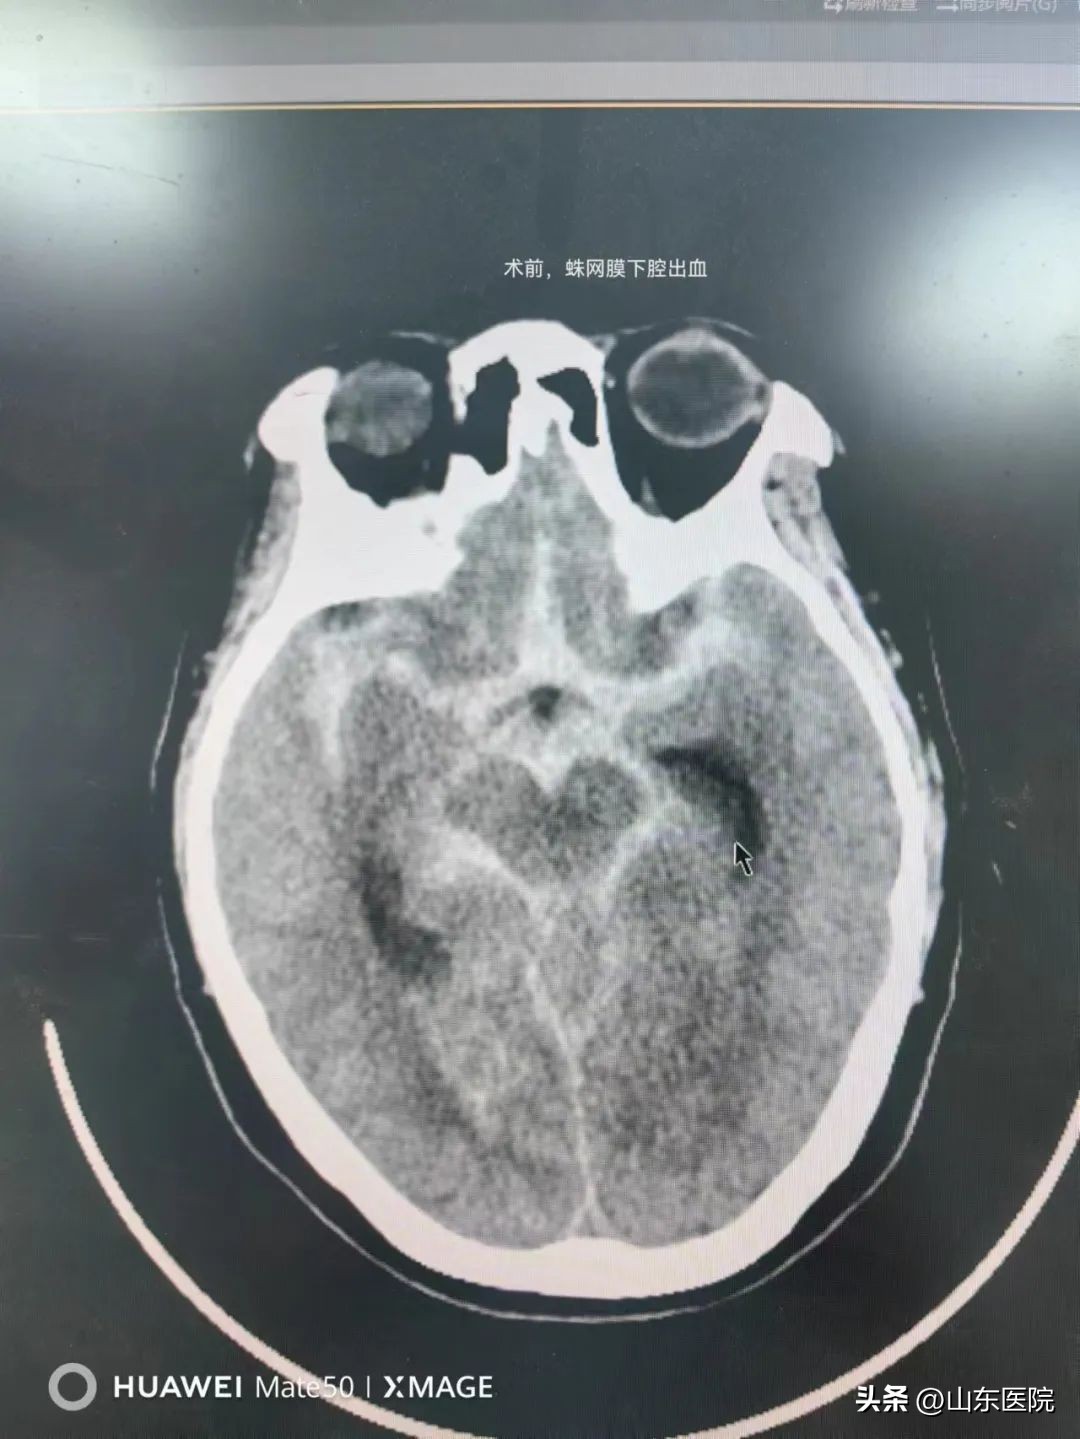

故事回溯到事发前,5月11日晚,范阿姨突然出现头疼,逐渐出现意识障碍,于是紧急来院。经过杨鹏医师的检查诊断为自发性蛛网膜下腔出血,高度怀疑动脉瘤,随时有再出血及呼吸心跳骤停的危险。

和家属沟通后,神经外科国泉、姜宗臣两位医师带领介入团队急症给予全脑血管造影术,证实了脑动脉瘤的存在。颅内动脉瘤是一种常见的脑血管疾病,容易破裂出血,是颅内的“不定时*弹炸**”。国泉、姜宗臣两位医师立即给予了动脉瘤弹簧圈致密栓塞术。手术顺利,但因为患者术前出血较多,患者出现了急性脑积水,意识障碍仍逐渐加重,一度出现呼吸衰竭, 治疗小组再给予脑室外引流术,术后经过了发热,肺内感染,静脉血栓,低蛋白血症等各个凶险的关口,患者术后逐渐清醒,目前已康复并出院。